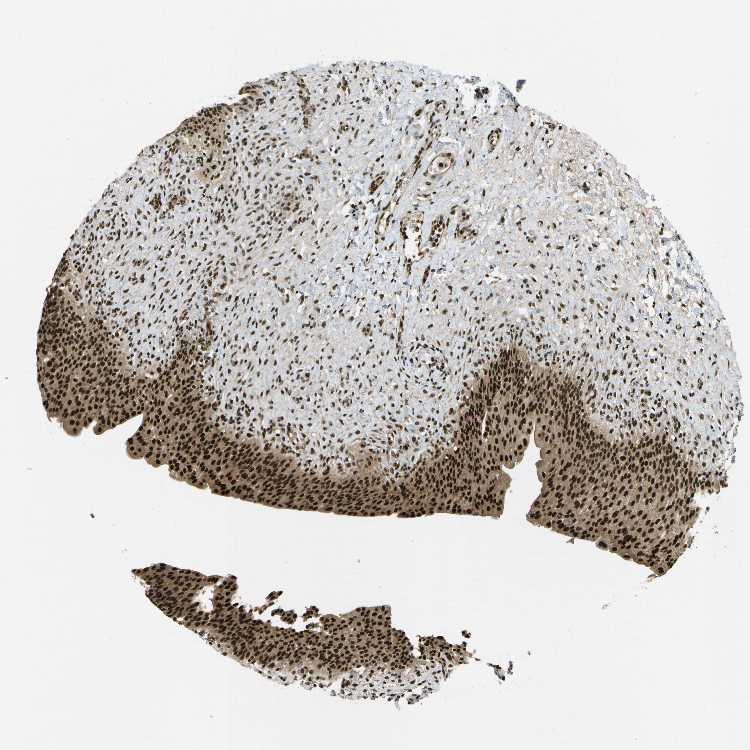

URINARY BLADDER - Antibody stainingi

Antibody staining in the annotated cell types in the current human tissue is reported as not detected, low, medium, or high, based on conventional immunohistochemistry profiling in selected tissues. This score is based on the combination of the staining intensity and fraction of stained cells.

Each image is clickable and will lead to virtual microscopy that enables deeper exploration of all samples and also displays staining intensity scores, fraction scores and subcellular localization as well as patient and tissue information for each sample.

Antibody HPA016949

Urothelial cells High